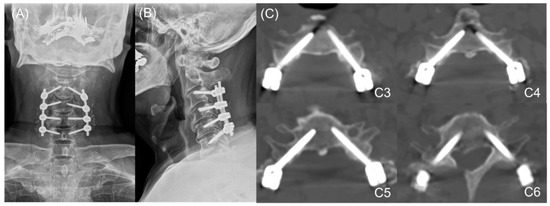

2. Materials and Methods

3. Results